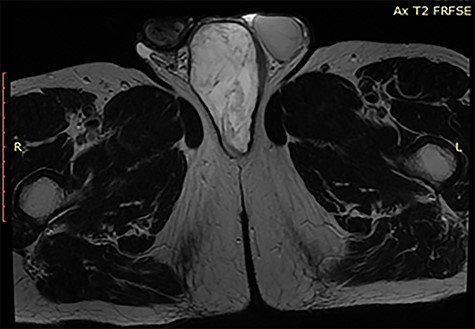

A 57-year old male presented to surgery outpatient clinic of the hospital with scrotal mass. His initial review of systems was negative for any complaints except a feeling of heaviness at the scrotum. On clinical examination, the mass was mobile and did not transilluminate. The lesion had gradually increased in size during the last 2 years. The overlying skin was normal. The patient’s medical history like his family was normal. Ultrasound revealed a weak and heterogeneous echogenic mass (Fig. 1), and after the imaging with computed tomography (CT) and magnetic resonance imaging (MRI) (Figs 2 and 3) of the pelvis, we proposed surgical excision of the mass. Preoperatively, there was no suspicion of the diagnosis of aggressive angiomyxoma. Moreover, the differential diagnosis was between lipoma and testicular malignances. We preferred a perineal procedure with patient in lithotomy position; also the team was composed of a general surgeon and an urologist. We extracted a mucoid mass en bloc with free macroscopic margins. The mass was 11 cm in its max diameter, this was extended to the pubic symphysis and displaced the urethra without infiltrated it. The histological examination revealed small spindle-shaped cells without atypia or mitosis proliferating in an edematous to fibrous stroma and numerous small- to medium-sized thick-walled vessels. Around the mass was a smooth muscle integument. The neoplasmatic cells had the expression of desmin, CD34, S100, vimentin, smooth muscle antibody, estrogen receptor 40%, progesteron receptor 20% and Ki67-5%. Postoperatively, our patient had an uneventful recovery. A postoperative SPECT was negative for metastatic disease, and the 2-year follow-up is negative for recurrence of the disease.

Aggressive angiomyxoma is a rare entity most frequently between reproductive age women (male/female: 1/7) [3]. Aggressive angiomyxoma or deep angiomyxoma as referred by the world health organization is a mesenchymal malignancy first described in 1983 by Steeper and Rosai. This tumor most commonly derived from the female vulvar region, pelvis and perineum and male scrotum and inguinal region, but there are a few cases with non-pelvic invasion [4, 5]. At the most cases, angiomyxoma is an asymptomatic gradually enlargement mass, the symptoms in most patients are swelling without pain, abdominal distention, hematuria or vaginal hemorrhage in women. In our case, the only symptom was the palpable mass of the scrotum [1, 6]. The differential diagnosis of the palpable mass of scrotum in men patients is between perineal cyst, inguinal hernia, hydrocele, lipoma, abscess, leiomyoma, leiomyosarcoma, liposarcoma, testicular tumors or unidentified masses. The examination of the mass should begin with ultrasound tomography, which demonstrates a hypoechoic, well-demarcated mass with multiple thin echogenic internal septa, and for more detailed imaging, we can use computed tomography or magnetic resonance imaging, which on T2 weighted image has high signal intensities, or digital subtraction angiography to recognize the details of mass structure, to identify the relations between the near anatomical structures in order to organize the operation. Aggressive angiomyxoma has a distinctive imaging appearance of swirled or layered pattern in the tumor after enhancement on CT and MRI [7–9] with intravenous contrast injection. Preoperative diagnoses require high degree of suspicion. There are a few cases with preoperative histological diagnoses with CT assisted biopsy, but in most described cases the diagnosis was made postoperatively with the histological examination of the mass. Histologically, the typical findings include stellate to spindle-shaped tumor cells with fibromyxoid stroma and hyalinized thin-to-thick wall vessels and no necrosis or cystic changes, and the immunohistochemical studies show the expression of vimentin, smooth-muscle actin and CD34 to be strongly positive, the desmin, estrogen receptors and progestin receptors to be median positive, but mostly negative for S-100 and CD68 [3]. The more effective treatment for aggressive angiomyxoma is the radical free margin surgical excision. However, the risk of local recurrence is high especially within 2–3 years after the first operation. A reason for local recurrence is the incomplete surgical excision; however; Chan et al. [6] report no difference in recurrence in patients with negative margins compared with those with positive margins. In general, aggressive angiomyxoma has no tendency for distal metastases, but there was a report of a case with lung and mediastinum metastases. Radiation therapy has proposed as a monotherapy or as control of multiple recurrences after surgical excision, with poor results [10]. Chemotherapy has poor results in aggressive angiomyxoma because of the slow progress of the disease. Monotherapy may has a role in control of these tumors because of the expression of ER and PR receptors.